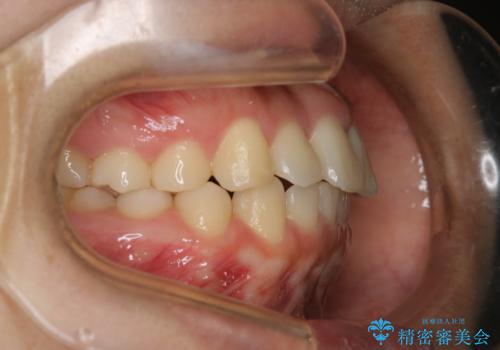

- 前歯が捻転していることを主訴に来院された方です。元々は部分矯正をご希望されていましたが、噛み合わせ等総合的に治療していくためインビザラインにて全顎的に治療を行うこととしました。

元々は上の前歯部の捻転のみの治療をご希望されていましたが、下の前歯もがたつきがあることや噛み合わせがかなり深いことを説明しました。後戻りのリスクを抑えるために全顎的な治療をご提案しました。

捻転していた上顎前歯部の仕上がりにこだわり、何度か修正を行ったため、満足のいく仕上がりになったと大変喜んでいただけました。